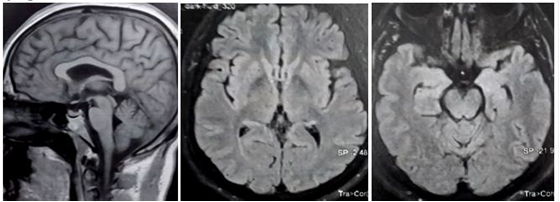

Observation: A 35-year-old man progressively presented gait disturbances with postural instability leading to falls. On examination: Akineto-rigid parkinsonian syndrome (PS), primarily axial, associated with vertical gaze palsy, head backwards tilt and postural instability without tremor. There was a slight frontal syndrome, irritability and dysphagia. The biological assessment (autoimmunity, copper and CSF testing) was correct. Brain MRI of the onset [figure1] did not show mesencephalic atrophy, nor signal abnormalities of overload disorders (Wilson's disease (WD), neuroferritinopathy). The patient underwent a therapeutic test (L-dopa 300 mg/d) over three months, without significant improvement. We then added ropinirole, rivastigmine and paroxetine. Despite the given therapeutics, no remarkable changes were noticed.

There has been a slight frontal syndrome (Palmomental and Snout reflex were present) and bulbar syndrome (dysphagia), without major cognitive disorders apart from irritability. The biological assessment, including autoimmunity, copper testing and CSF analysis with iso-electro-focalisation, was correct. Video-oculography has not been performed. Brain MRI, at the onset, did not show mesencephalic atrophy, nor parenchymal signal abnormalities in favour of overload disorders (Wilson's disease or neuroferritinopathy). The patient underwent a therapeutic test with L-dopa (300mg/d) over three months, however, there was no significant improvement. After that, we added ropinirole (4mg/day), rivastigmine solution (3mg/d) and paroxetine (20mg/d). Despite the given therapeutics, there were no remarkable changes in the patient's symptoms.

A regular brain MRI control was planned to look for possible atrophy of the midbrain that may not be found at the start of the disease.